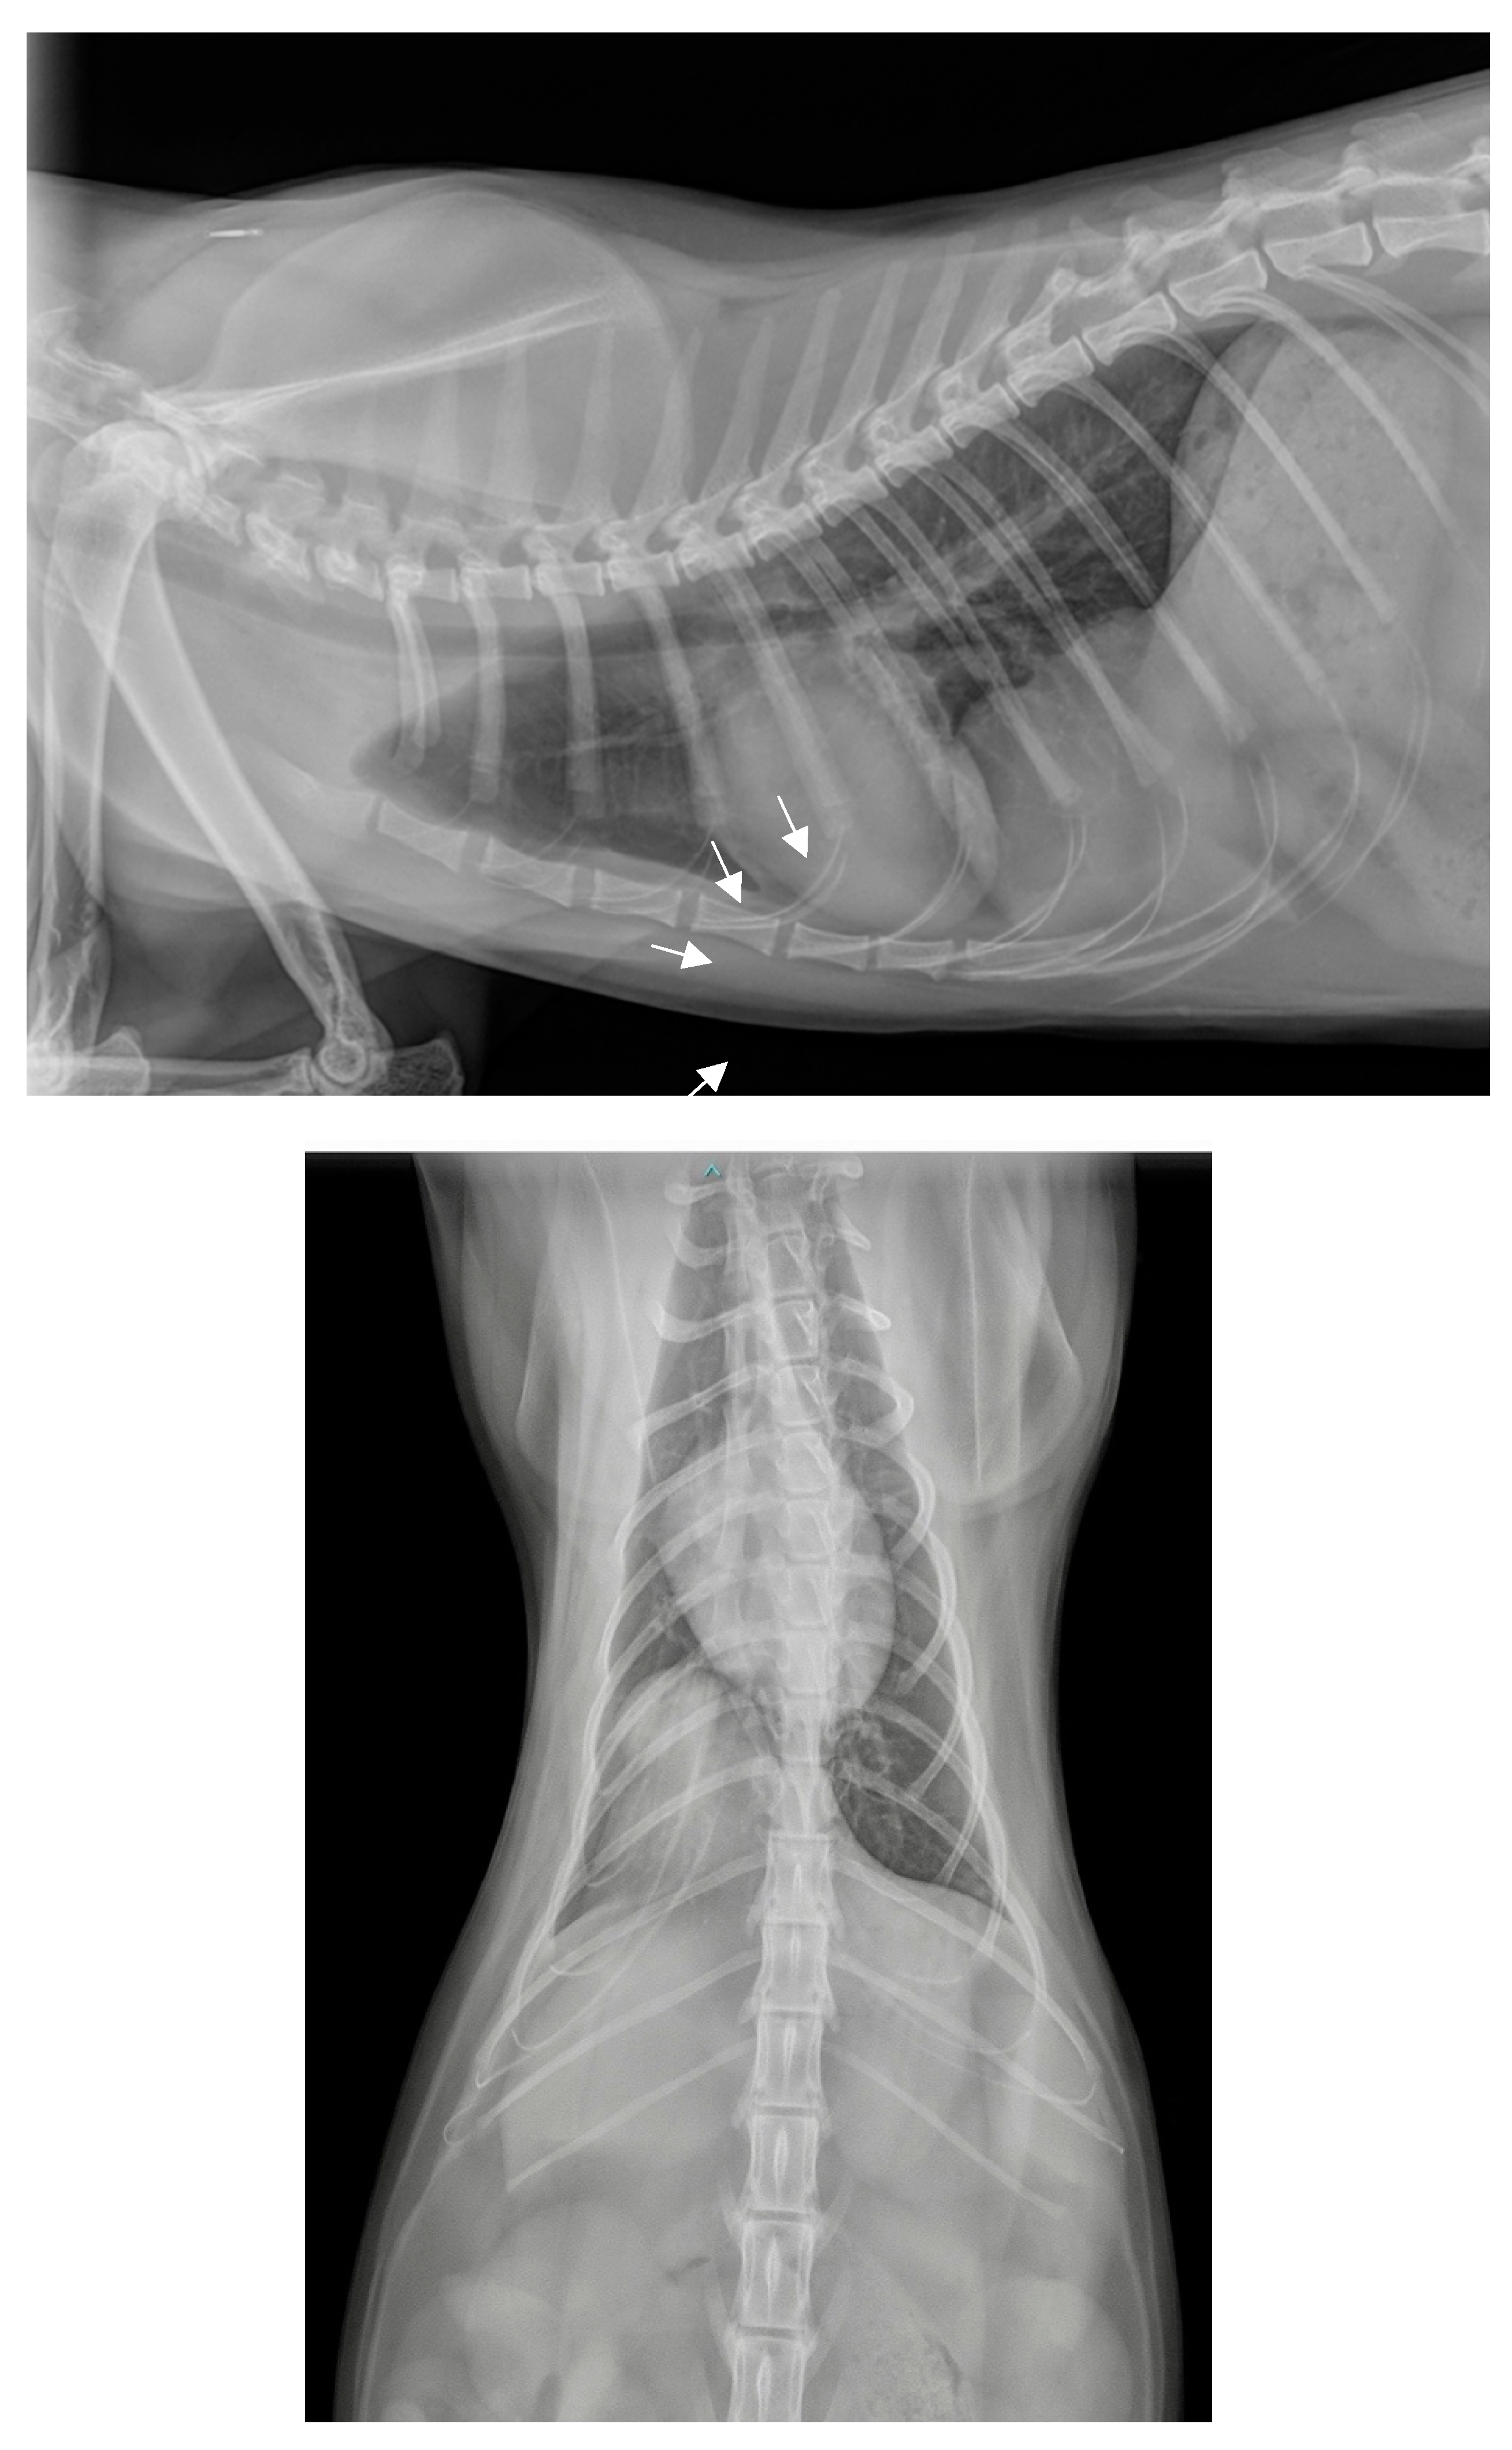

Subsequently, a positive contrast peritoneography was carried out by injecting transabdominally, on the linea alba, 2 ml/kg of an iodine derivative, iopamidol, Iopamiron®, at a concentration of 300 mg/ml, at room temperature and then placing the animal in sternal recumbency with the pelvis elevated (Figure 2a,b).

The contrast medium distributed well throughout the peritoneal cavity and was also observed in the usual thoracic projection area. However, it did not diffuse throughout the entire thoracic cavity; rather, it appeared to be contained by a membrane or by the deformed diaphragmatic muscle. The contrast product having been injected into the abdominal cavity and found at the location of the abnormal structure identified on the plain radiographs, it was now proven that this structure was of abdominal origin. Given the location, it could have been a part of a hepatic lobe, the falciform ligament, the omentum, the intestine, the stomach, the pancreas or the spleen.

2.3. Diagnosis

These findings led to the diagnosis of a diaphragmatic hernia. The very circumscribed nature of the hernia, and particularly the fact that the contrast medium did not disperse throughout the entire thoracic cavity, suggested a specific type of congenital diaphragmatic hernia known as “pleuroperitoneal hernia” or “true diaphragmatic hernia”, in which the involved organs are enclosed within a hernial sac. The hypothesis of a peritoneopericardial hernia was ruled out because, in such a case, the contrast medium would have spread into the pericardial sac. Similarly, had there been a diaphragmatic tear, the contrast medium would have disseminated throughout the pleural cavity. This case was deemed an incidental discovery of a congenital anomaly predating the traumatic event.

There were no intraoperative or postoperative complications. Immediate postoperative radiographs confirmed hernia reduction and showed the persistence of a mild pneumothorax (Figure 3a,b). The hernial sac, which was not removed, was clearly visible on the lateral view (white arrows), it contained a small amount of air. The contrast medium was drained by the parietal and visceral peritoneum, then eliminated by the kidneys, it was subsequently visible in the bladder.

Figure 2. Thoracic and abdominal radiographs obtained 10 minutes after contrast medium injection. a. Lateral view in right decubitus position. b. Front view (dorso-ventral).

Figure 3. Thoracic and abdominal radiographs immediately postoperatively. a. Lateral view in right decubitus position. b. Front view (dorso-ventral).